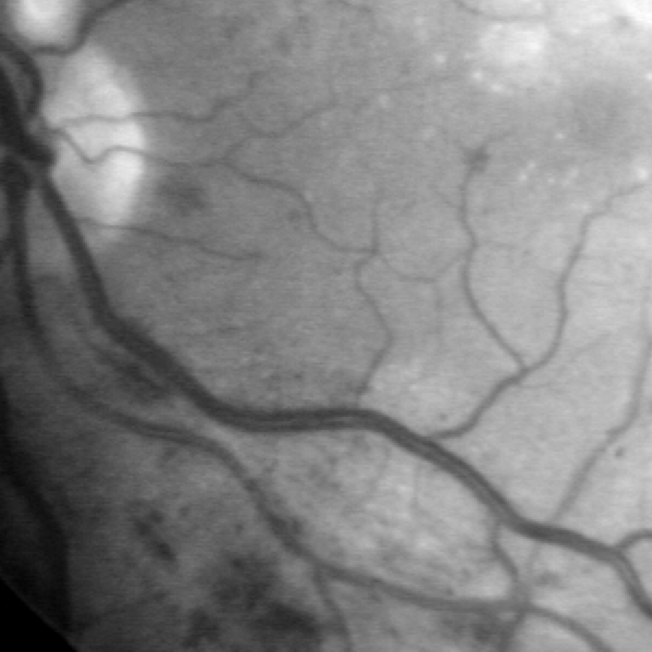

Medical images suffer from the distribution shift caused by the discrepancy in imaging acquisition protocols. Images can appear in different contrast, resolution and range of intensity values, even within the same modality. A set of examples is shown in Fig. 1. This obstacle severely impedes the learning-based algorithms reaching clinical adoption. Therefore, much effort has been spent on solving the domain generalization (DG) problem so that the deep models can robustly work on out-of-distribution (OOD) data. There are three major types of solutions: data augmentation [23, 18], meta-learning [6, 14] and domain alignment [24]. The first two strategies aim to improve the model’s generalizability by either augmenting the source domain with additional data or replicating the exposure to OOD data during training. In contrast, the domain alignment strives to align the distribution of the target domains in either image [8] or feature space [1, 15].